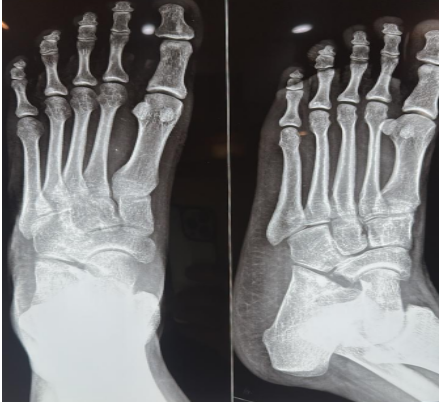

An 18-year-old female cricket athlete presented with a gradually increasing swelling and pain over the anterolateral aspect of the right ankle for 5 years. She had a history of a lipoma on the dorsum of the foot 5 years prior. Pain was aggravated during running and dorsiflexion, limiting sports activity. On examination, a soft, non-tender swelling was palpable over the anterolateral ankle with restriction of dorsiflexion, terminally with restricted hindfoot movements. On local examination, a soft, non-tender, well-defined swelling measuring approximately 6 × 3 cm was noted over the anterolateral aspect of the right ankle. The overlying skin was normal with no signs of inflammation. There was a terminal restriction of dorsiflexion as well as inversion–eversion. Distal neurovascular examination was normal. X-rays were taken for further evaluation, which showed calcaneonavicular coalition (Fig. 1).

Figure 1: Calcaneonavicular coalition.